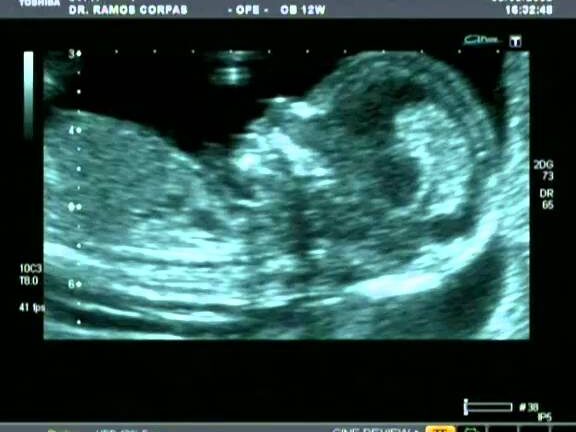

La translucencia nucal es un examen que se realiza durante el primer trimestre del embarazo para evaluar el riesgo de malformaciones y alteraciones genéticas en el feto. Se utiliza como una herramienta de screening y puede indicar la necesidad de realizar otros exámenes más específicos.